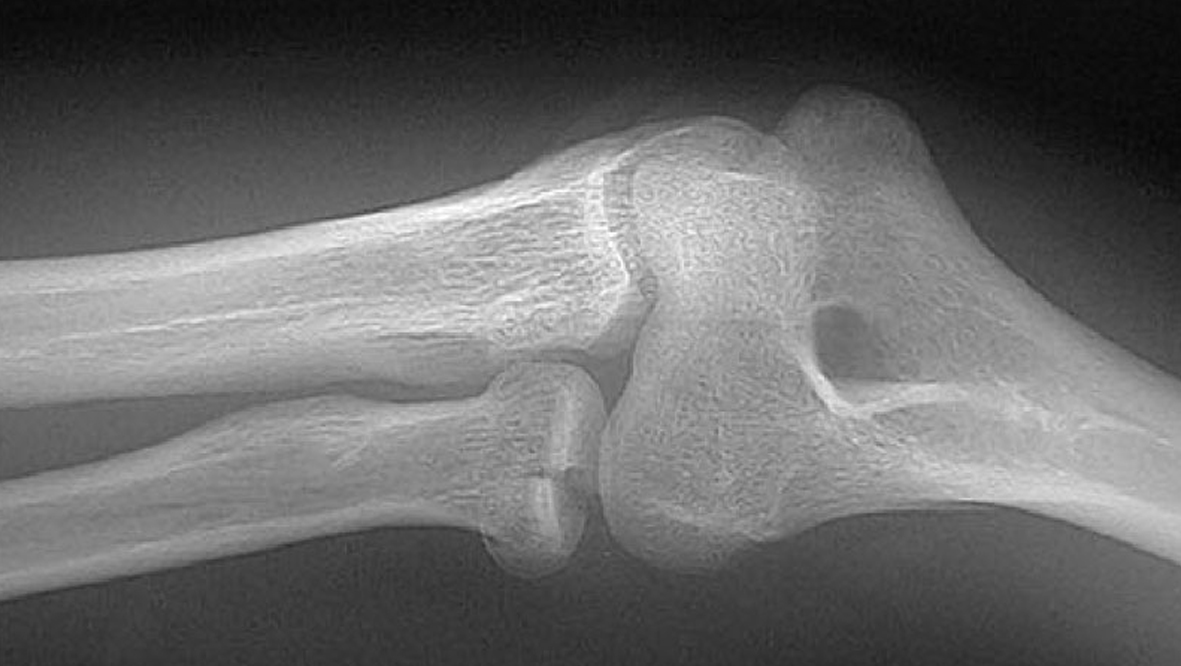

Se si sospetta una lesione con coinvolgimento dell’osso, il primo esame da eseguire è la radiografia standard. Per meglio definire fratture complesse e con eventuale coinvolgimento articolare, la tomografia computerizzata (TAC) offre la maggiore quantità di dettagli.